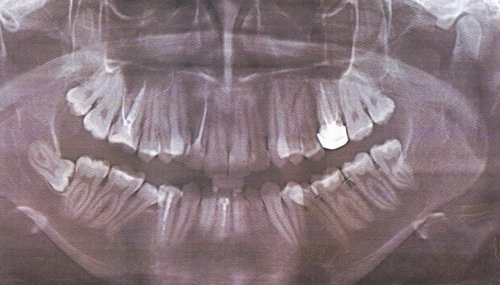

Около 3-х лет назад мне удалили нервы из верхней правой шестерки. Спустя 2 года воспалились корни, т.е. около 9 месяцев назад перелечивали корни, поставили коронку. Месяц назад зуб снова заболел, оказалось воспаление под корнем.

Хотелось бы узнать, действительно ли есть воспаление? И вообще в целом ситуацию насчет этого зуба, какое лечение следует предпринять? Есть 2 панорамных снимка.

Действительно, в зубе имеется хронический воспалительный процесс, причина — некачественное лечение каналов. Зуб будет лечиться в несколько посещений, и при квалифицированном подходе его вполне можно спасти.